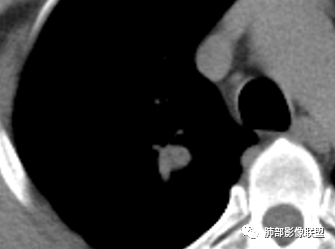

影像,气管憩室,两肺尖都有病灶,长索条

纵隔窗提示内侧部分密度不够实

内部小点状影提示可能支气管腔内粘液栓

遗憾的是:层厚太厚,无重建

这些是否是边界清楚GGO?

南边:2、不踏实的地方:GGO是不是容积效应所致?如果薄层,边界清楚GGO,就考虑继发瘢痕癌

因此我们需要的是:薄层、重建,看GGO边缘、看整体形态

结果:结核合并真菌(曲霉菌)感染